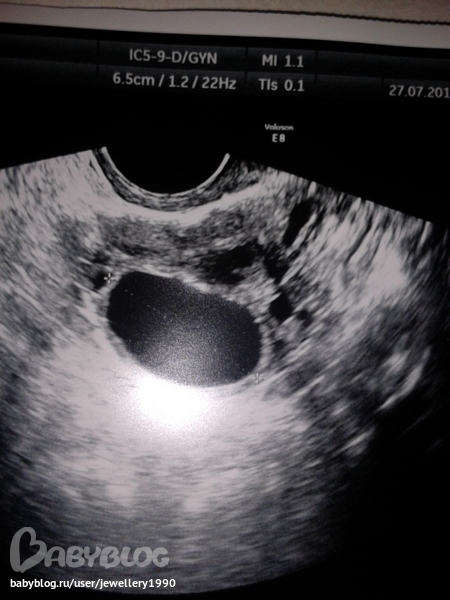

Может кому невидно я напишу что разобрала! область после операц. рубца б.о толщина миометрии - 4 мм

М-эхо 9мм, контуры неровные

правый яичник 41 на 26 на 35 мм

левый яичник 48 на 32 на 46 мм

в самый верхней фотки узи на бумажке где написано матка вот такие показатели там что то написано я не разобрала и 53 на 42 на 48 мм